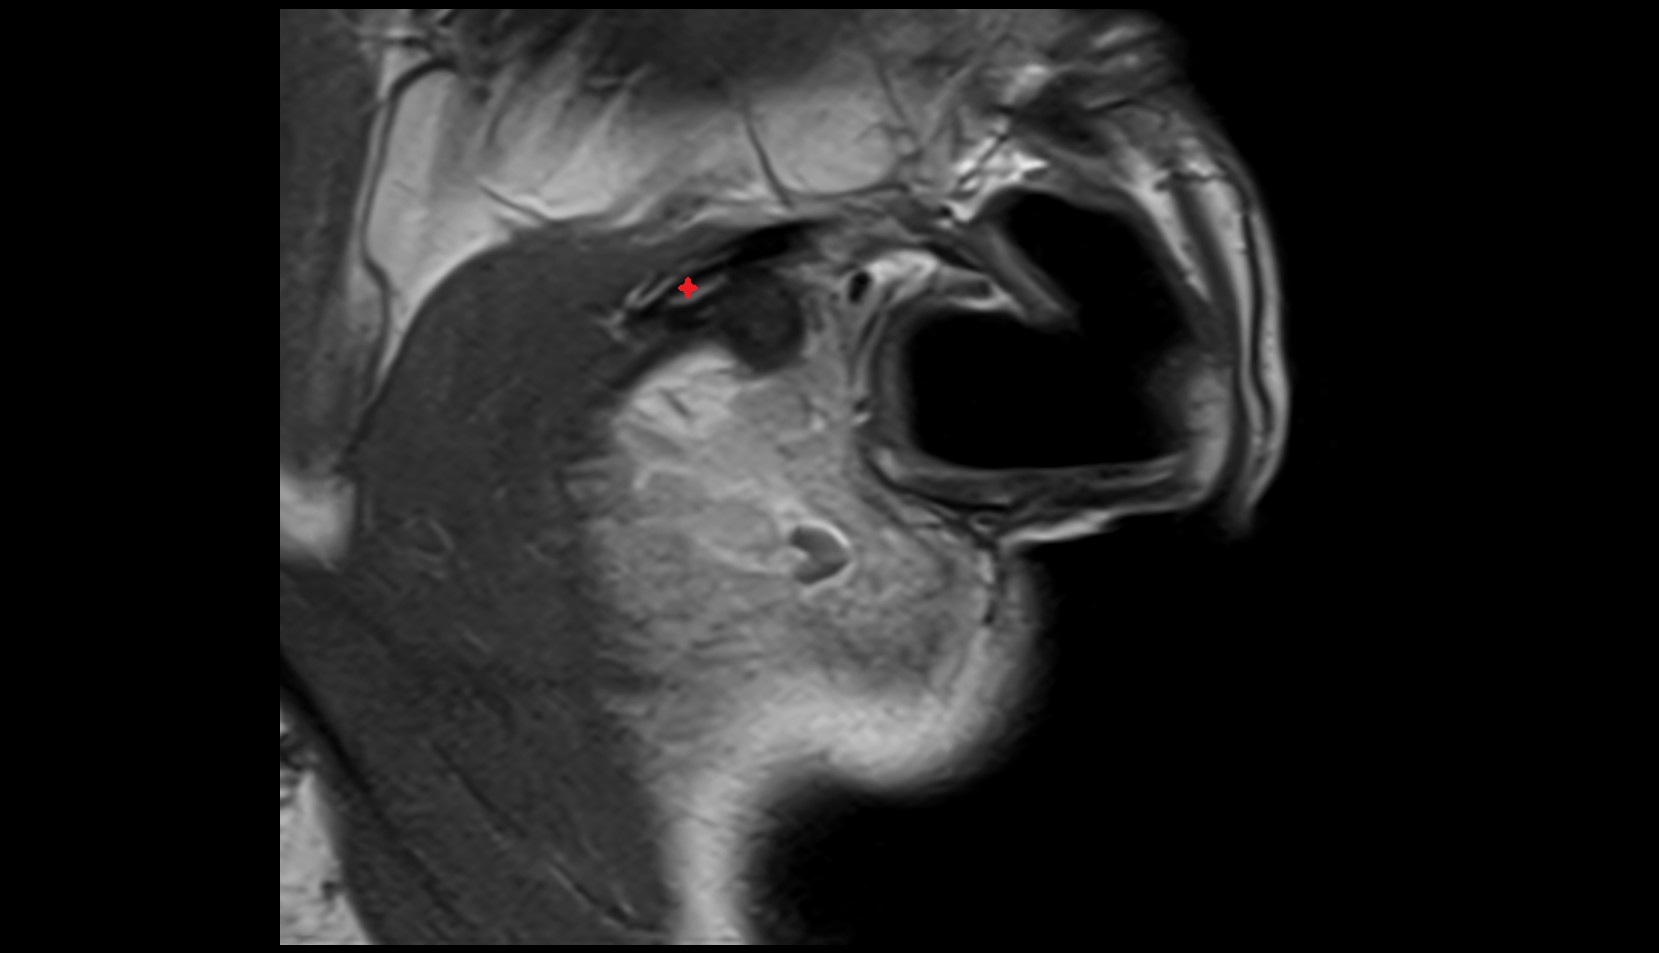

- Temporomandibular joint

- Articular disc of temporomandibular joint

- Articular eminence

- Mandibular condyle

- Mandibular fossa

- Superior head of lateral pterygoid muscle

- Inferior head of lateral pterygoid muscle